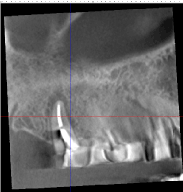

To help in a more precise diagnosis, high definition cone-beam computed tomography(CBCT) was taken. A J-shaped lesion at the apical portion of the distobuccal root of the maxillary right second molar, as seen in the CBCT, raised the possibility of root fracture or an unhealed periapical lesion (Figure 5). This lesion could not be seen on the two-dimensional radiographs taken before. There were also indications of possible communication of the apical portion of the maxillary right first bicuspid with the maxillary sinus, as evidenced by the thickening of the sinus membrane (Figure 6). Mandibular right second bicuspid and second molar did not have any visible fracture, however, the patient’s complaint of extreme pain on those teeth together with the compromised remaining tooth structure, made their extraction and replacement with the implant-supported fixed prosthesis the most logical treatment option. The pain had been intermittent, lingering, and more profound at night time. The teeth responded negatively to routine tests.

Figure 5. CBCT of the maxillary right second molar showing a J-shaped lesion on distobuccal root.

Figure 6. CBCT of the maxillary right first bicuspid showing its proximity to the maxillary sinus.